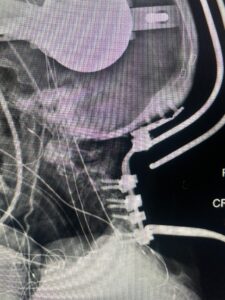

This is a 59 year-old female with a history of cerebral palsy and a prior C3-C7 posterior cervical laminectomy and instrumented fusion two years prior. She did ok until she developed progressive weakness of all four extremities and numbness. Imaging revealed she had a significant breakdown above the fusion at C2-3 with a grade 2-3 spondylolisthesis of C2 on C3 with severe spinal cord compression (Fig. 9). It was surprising the degree of anterior fusion induced by the posterior fusion from C 3-C 7 (Fig. 10). Because of her progressive neurological dysfunction in a patient who was already compromised because of her cerebral palsy, it was clearly necessary to decompress from occiput to C 3. We utilized her prior lateral mass screws although we removed bilaterally the C7 screws to reduce the fulcrum-effect on the C7-T1 junction as the C 6-7 level was solidly fused. We performed an occiput to C 6 fusion with occiput to C3 laminectomy (Fig. 11) Post operatively we had good placement and alignment (Fig. 12) The patient went to rehab with improvement of strength and numbness particularly in hands.

Fig. 12: Intraoperative lateral X-ray demonstrating good placement of occipital-cervical construct